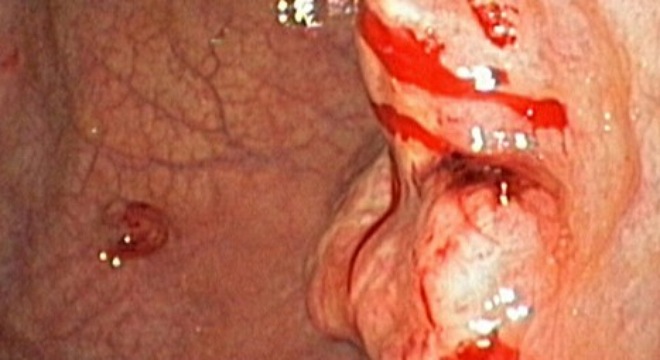

Old  Default Có dấu hiệu này bạn nên đi khám ung thư dạ dày ngay!!!

Ung thư dạ dày là căn bệnh gây chết người nhiều thứ 3 ở Việt Nam. Triệu chứng của ung thư dạ dày tuy khó nhận ra nhưng không phải là không thể nhận ra. Hãy chú ý nếu phát hiện ra triệu chứng nghi ngờ là ung thư dạ dày, bạn hãy đi khám thật sớm để có thể tầm soát căn bệnh này thật tốt.